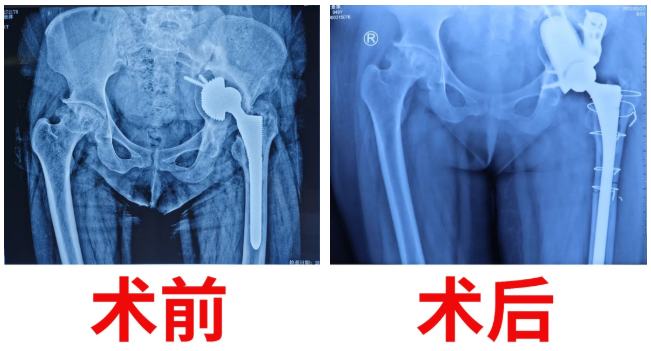

在骨科醫(yī)護(hù)團(tuán)隊(duì)的悉心照顧和鼓勵(lì)下,術(shù)后復(fù)查顯示假體植入非常理想,患者髖臼骨缺損填補(bǔ)滿意、關(guān)節(jié)假體復(fù)位滿意,同時(shí)也成功地消除了肢體不等長(zhǎng)的這個(gè)差距,疼痛感完全消失,髖關(guān)節(jié)各個(gè)方向被動(dòng)活動(dòng)基本達(dá)到要求。患者手術(shù)當(dāng)天就坐起了身,術(shù)后第10日即可下床扶柺慢行。